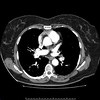

Over 53,000 people were enrolled in the National Lung Screening Trial, 26,700 of whom received annual low-dose CT scans, 26,700 undergoing annual chest films, with additional scans and some invasive procedures for radiographic abnormalities. The NLST results were published in the New England Journal of Medicine in August 2011, and showed:

Low-dose CT scanning reduced death from lung cancer by a relative 20% compared to screening with chest X-rays (247 vs. 309 deaths per 100,000 person-years).

One lung cancer death was prevented for every 320 people screened with low-dose CT.

39% of patients had at least one abnormal CT scan among the 3 annual scans.

Among those with abnormal CT scans, 96% were determined not to be lung cancer (false positives).